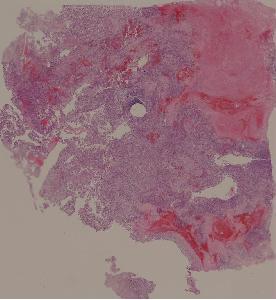

36. Lymphoma